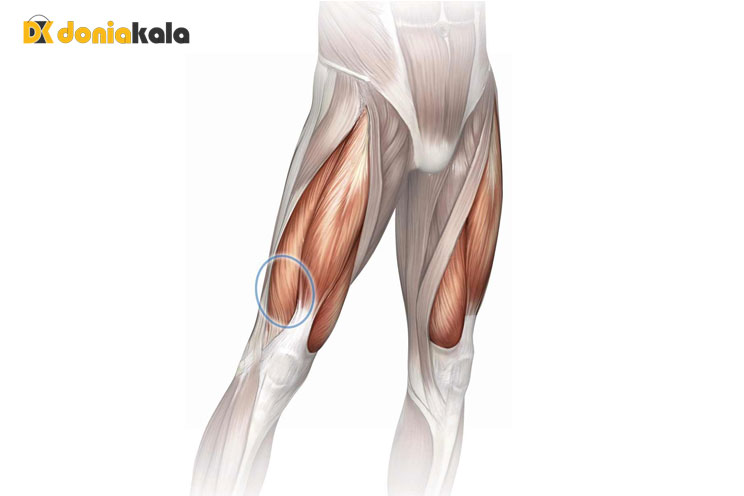

تاندونوپاتی Tendinopathy: تاندونوپاتی به آسیب های تاندون اطلاق می شود که اغلب منجر به درد، تورم و اختلال در عملکرد می شود که معمولاً در اثر استفاده بیش از حد ایجاد می شود. تاندون ها بافت های ضخیمی هستند که استخوان را به ماهیچه متصل می کنند. در مورد چهارگوش، این ماهیچه ها را به کشکک می چسبانند. دو نوع اصلی تاندونیت تاندونیت و تاندونوز هستند. تاندونیت التهاب تاندون را توصیف می کند، در حالی که تاندونوز به تحلیل رفتن تاندون اشاره دارد. هر دو آسیب دردناک هستند و می توانند باعث از دست دادن انعطاف پذیری شوند.

اشک Tears: پارگی چهار سر ران زمانی را توصیف می کند که تاندون به طور جزئی یا کامل قطع می شود. این آسیب مشابه یک فشار است اما شامل کشش بیش از حد و پارگی است. در برخی موارد، آسیب ممکن است به صورت پارگی جزئی در جایی که تاندون در حال ساییدگی است شروع شود، اما سپس پیشرفت کرده و باعث پارگی کامل تاندون می شود. این آسیب ممکن است باعث جدا شدن عضلات از کاسه زانو شود، به این معنی که فرد نمی تواند زانوی خود را صاف کند. یک فرد ممکن است پس از پارگی تاندون چهارسر ران خود، همراه با احساس درد و تورم، صدای ترکیدن را بشنود. آنها همچنین ممکن است متوجه شکافی در بالای کاسه زانو شوند که در آن تاندون پاره شده است. درمان ممکن است متفاوت باشد اما می تواند شامل استراحت، فیزیوتراپی و جراحی باشد.